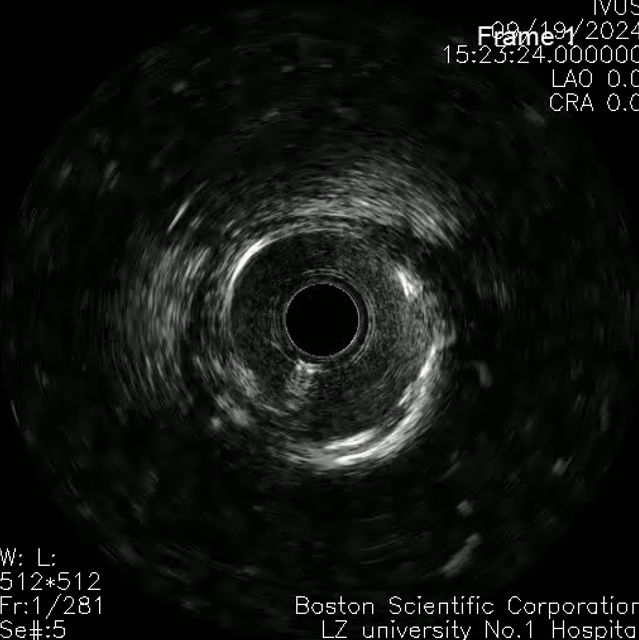

左主干-回旋支行IVUS检查;

回旋支近中段可见弥漫性狭窄伴有360°环形钙化;

回旋支开口面积2.1平方毫米;

左主干-前降支IVUS导管不能通过。

切割球囊切割后行IVUS检查提示钙化环有所断裂,回旋支开口狭窄仍严重,遂决定使用2.5mm NC球囊高压扩张。

回旋支支架植入后因支架及钙化原因,IVUS导管无法推送至中段以后,遂仅对回旋支开口支架IVUS检查。

回旋支开口支架后扩后行IVUS检查:支架贴壁膨胀良好。